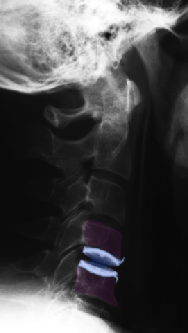

Πρόσθια αυχενική δισκεκτομή και τοποθέτηση τεχνητού αυχενικού δίσκου (μπλέ) Α6-Α7. Ακτινογραφίες με τον αυχένα σε ουδέτερη θέση (αριστερά), έκταση (κέντρο) και κάμψη (δεξιά). Αναδεικνύεται η κίνηση στο χειρουργημένο μεσοσπονδύλιο διάστημα. |